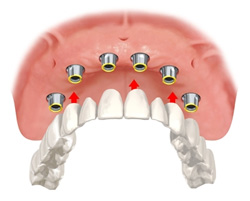

| All on 6 (All on 4 ) ※無歯顎をインプラントブリッジ固定式で回復 |

| 5本あるいはそれ以上のインプラントにより、フルブリッジを固定します。 |